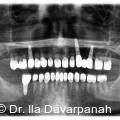

Die moderne Implantologie vereint heute funktionelle Stabilität mit höchsten ästhetischen Ansprüchen. Gerade im Frontzahnbereich hängt der Behandlungserfolg entscheidend von der präzisen Planung, der gewebeschonenden chirurgischen Umsetzung und einer frühzeitigen prothetischen Integration ab. Fotos: © Dr. Ila Davarpanah